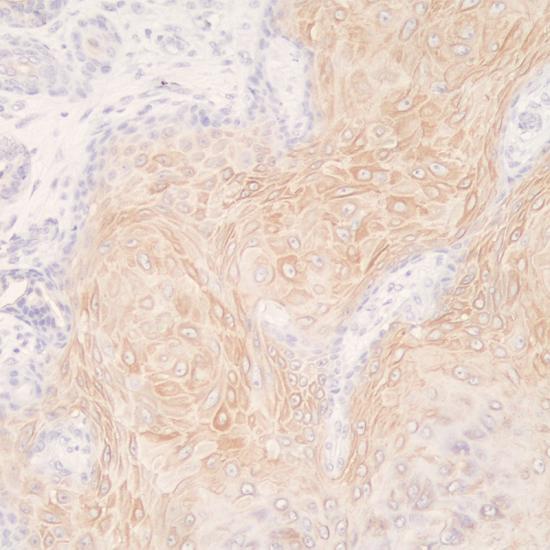

CK16在包括皮膚的許多復(fù)合上皮組織中組成型表達,在創(chuàng)傷愈合、牛皮癬和癌癥(鱗狀細胞癌)等有利于加強增殖或異常分化的條件下被誘導(dǎo)表達。CK16主要標記角化和增生的鱗狀上皮,主要用于鱗狀細胞癌的診斷。

• 陽性部位:

細胞漿

• 陽性對照:

皮膚癌